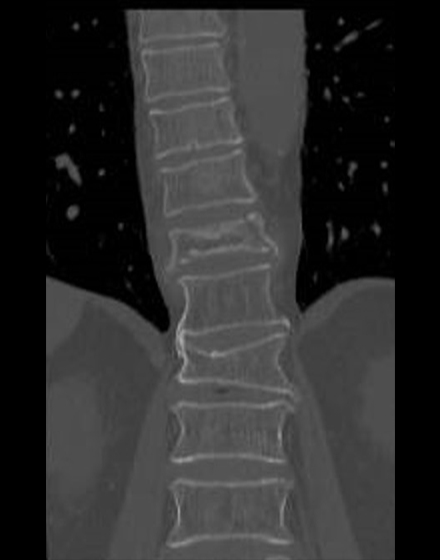

腰椎棘突起縦割式椎弓切除術

適応となる疾患:腰部脊柱管狭窄症、腰椎変性すべり症など

腰椎後方(背中)から椎弓、肥厚した黄色靭帯を切除し、硬膜管(馬尾神経の通っている管)の圧迫を解除します。棘突起を縦割することで腰背筋を骨から切離せず温存して、余分な組織のみ切除する低侵襲な手術を行います。従来の手術に比べ、術後の腰痛が軽度です。手術時間は1時間くらいで翌日から歩行が許可されます。入院期間は通常10~14日ぐらいになります。